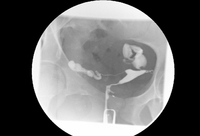

Hysterosalpingography (HSG) demonstrating bilateral hydrosalpinges

From the collection of Dr Jared C. Robins